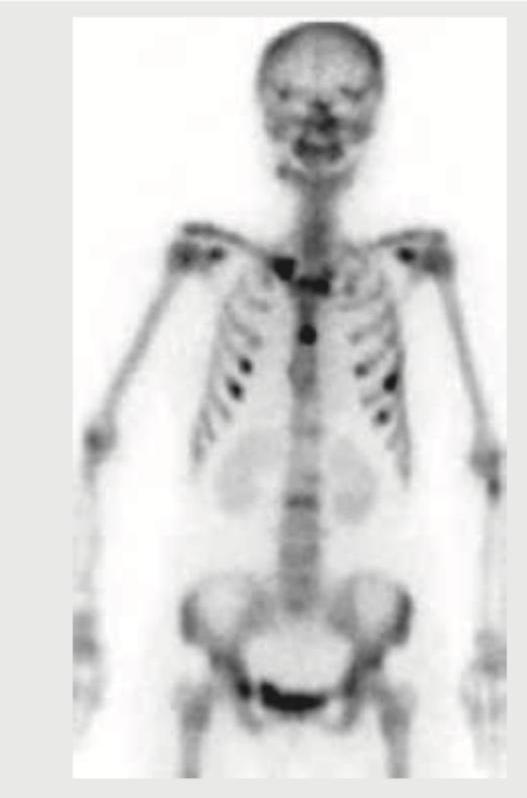

Explanation: ***Bone scintigraphy*** - This image displays a typical **bone scan** appearance, characterized by diffuse uptake throughout the skeletal system, with focal areas of increased tracer accumulation (hot spots) indicating increased bone turnover. - The visualization of the entire skeleton with this characteristic intensity and distribution of radioactive tracer is unique to **bone scintigraphy**. *Whole body MRI* - Whole body MRI images would exhibit detailed **anatomical structures** with varying signal intensities depending on tissue composition and MRI sequence, and would not show this uniform skeletal uptake pattern. - MRI is excellent for **soft tissue contrast** and bone marrow evaluation but does not produce the diffuse, radionuclide-based signal seen here. *Whole body CT scan* - A whole body CT scan provides highly detailed **cross-sectional anatomical images** based on X-ray attenuation, showing bone density and soft tissue. - It would not show the diffuse radionuclide uptake pattern characteristic of a bone scan but rather precise **structural details**. *Projectional radiography* - Projectional radiography (X-rays) would provide a 2D image of bone structures by showing differential absorption of X-rays, resulting in a distinct, shadow-like representation of bones. - It does not involve radioactive tracer uptake and therefore would not present this **diffuse uptake pattern** of the entire skeleton.

Explanation: ***18-F Fluoride*** - Among the listed PET tracers, **18-F Fluoride** is the bone-seeking radiotracer used for bone imaging - 18-F Fluoride PET provides high-resolution imaging of bone turnover and blood flow, and can detect stress fractures with high sensitivity - It localizes to areas of increased bone metabolism and osteoblastic activity, making it effective for detecting subtle stress injuries - **Note:** In routine clinical practice, **Tc-99m MDP (methylene diphosphonate)** is the standard tracer for conventional bone scintigraphy to detect stress fractures; however, among the PET tracers listed here, 18-F Fluoride is the appropriate bone imaging agent *FMISO (Fluoromisonidazole)* - **FMISO** is a **hypoxia tracer** used in PET imaging to identify areas of low oxygen tension - Primarily used in oncology to assess tumor hypoxia, not for bone or musculoskeletal imaging - Not indicated for evaluating stress fractures or bone metabolism *FLT (Fluorothymidine)* - **FLT** is a **proliferation tracer** that measures cellular DNA synthesis and proliferation - Mainly used in oncology to assess tumor growth and treatment response - Does not assess bone metabolism or detect stress fractures *64-Cu-ATSM* - **64-Cu-ATSM** is another **hypoxia tracer** used in PET imaging, similar to FMISO - Used to evaluate tissue hypoxia in cancer imaging - Not indicated for musculoskeletal injuries or bone metabolism assessment